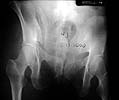

Here is an example of a Young-Burgess CMI (LC2/VS) pelvic fx, quite similar to the case presented by Adam Starr, fixed by ORIF posteriorly + anterior bridging exfix.

Preop AP

Preop Inlet

Preop CT

Postop AP

Postop Inlet

Postop Outlet

Nice reduction! That looks pretty darn good.

I guess you did him prone to open and fix the sacro-iliac joint fracture dislocation, then flipped him supine to place the ex-fix?